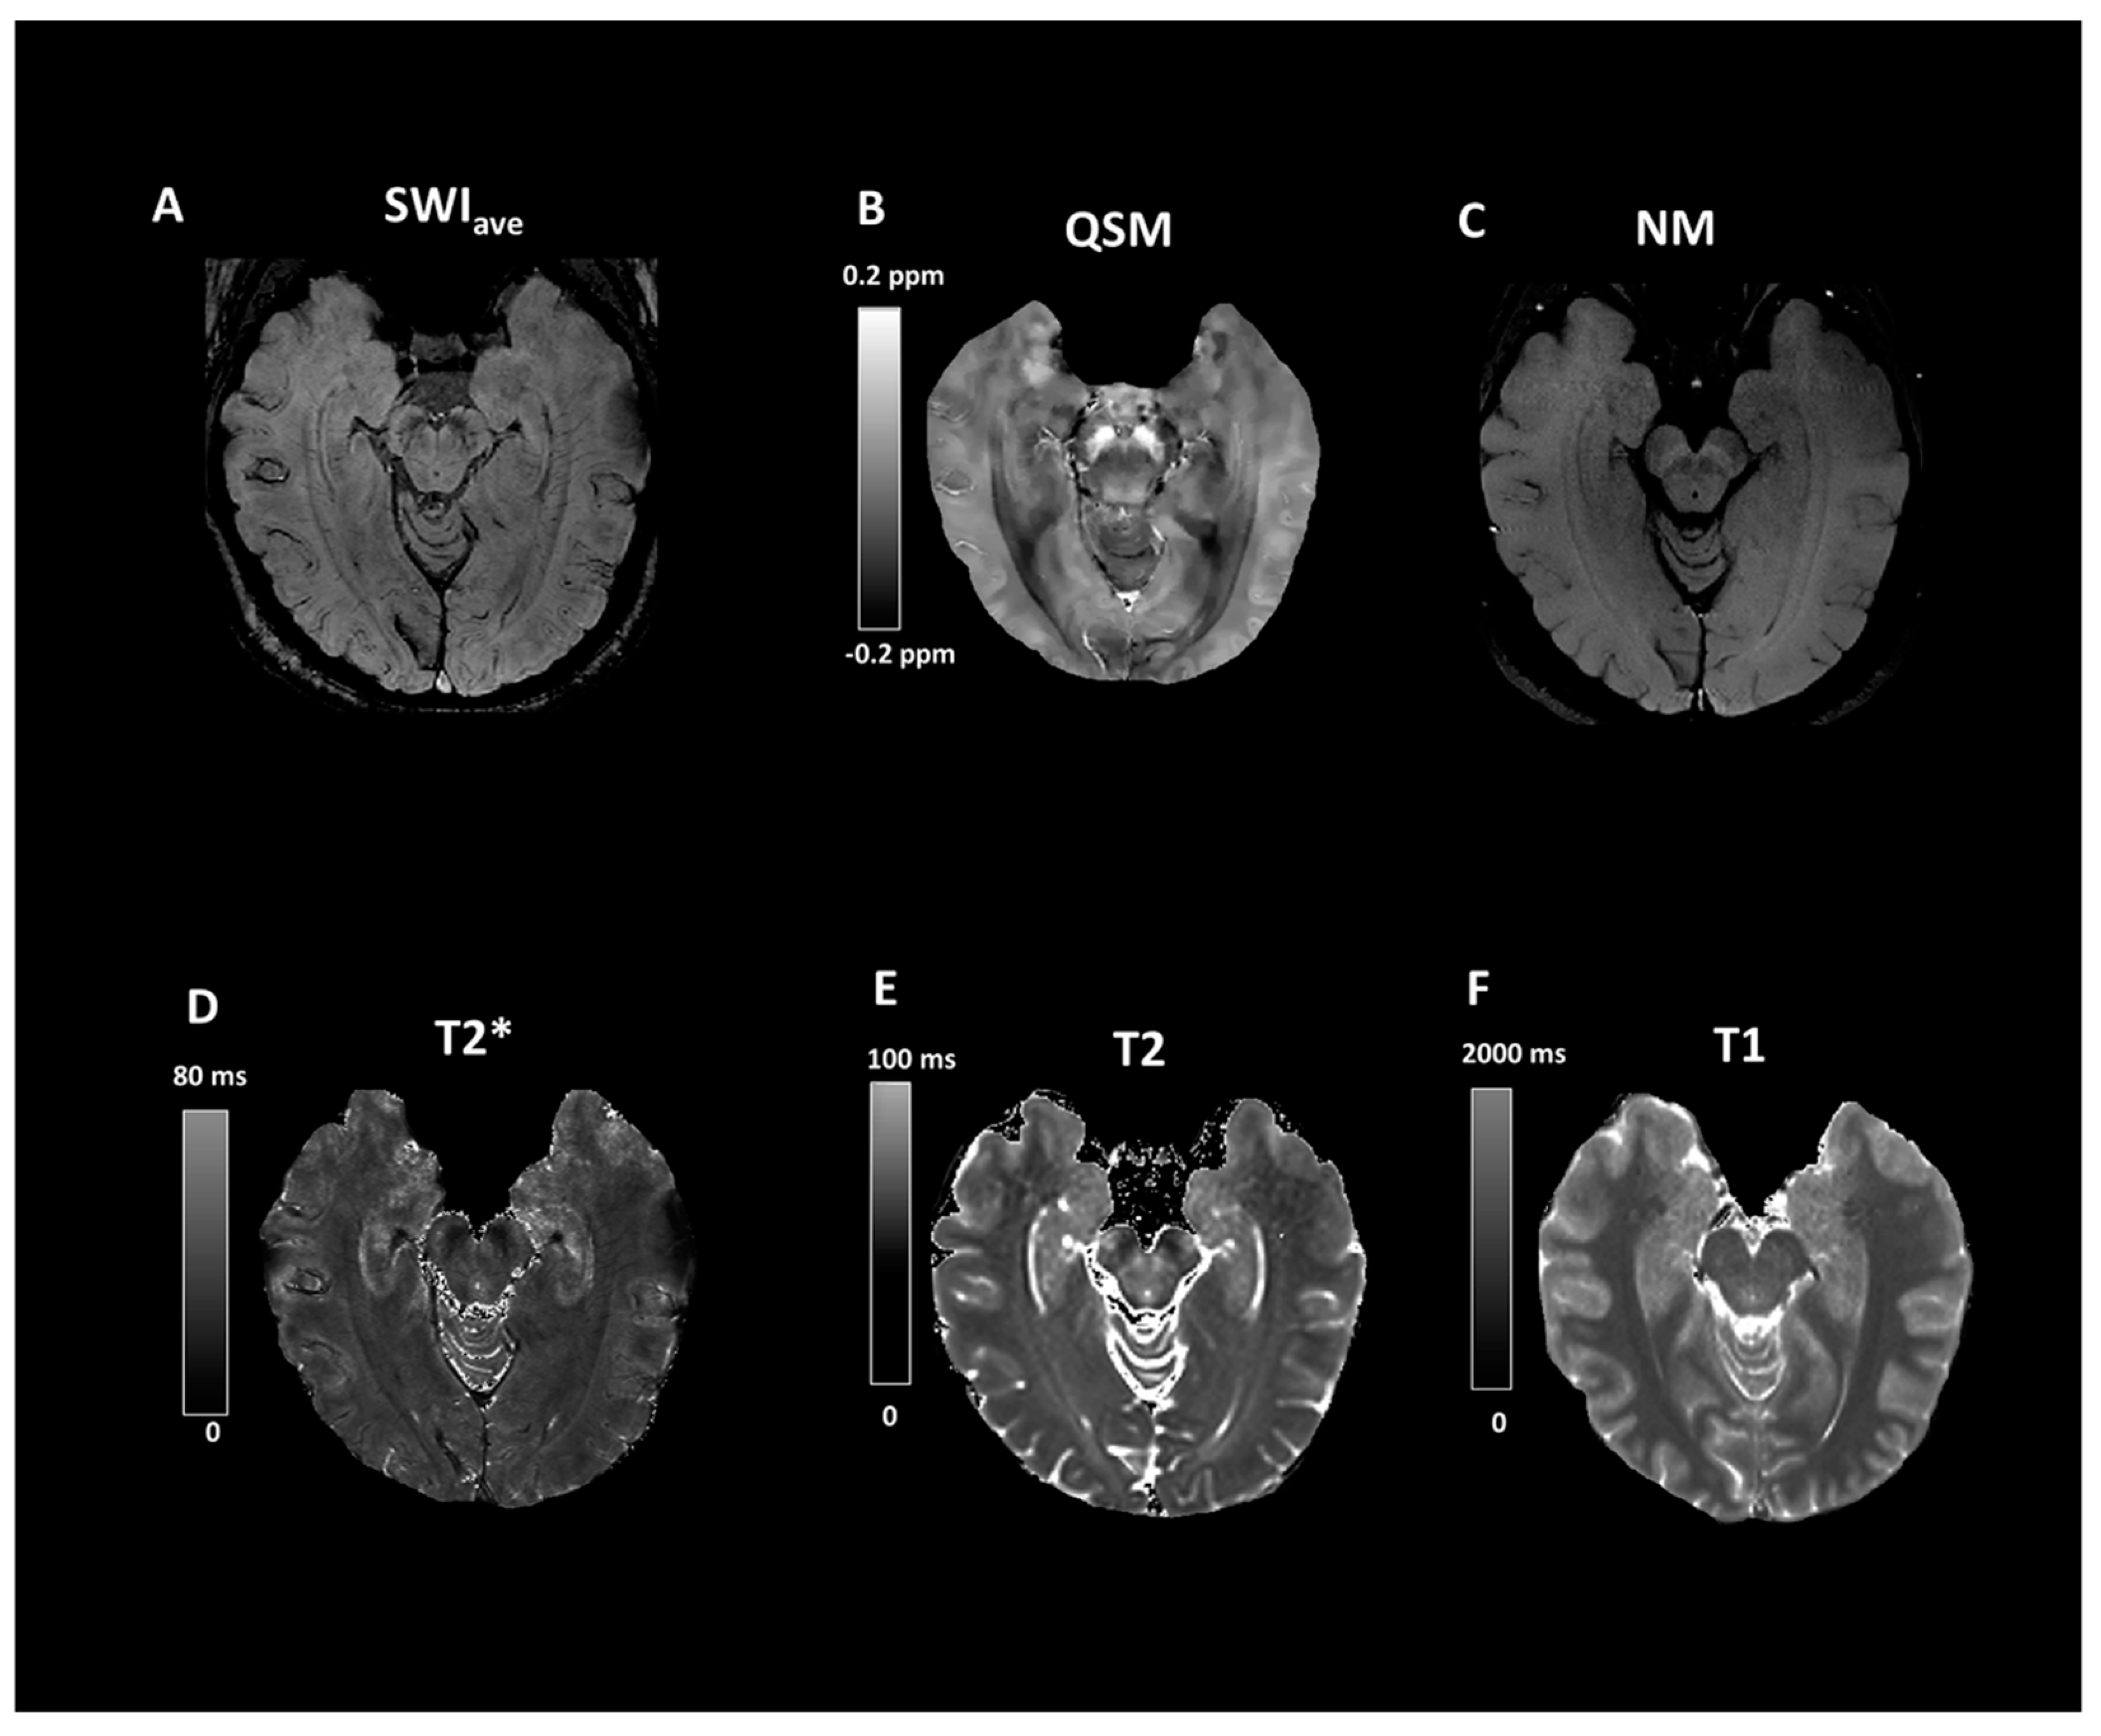

Evaluation of the Swallow-Tail Sign and Correlations of Neuromelanin Signal with Susceptibility and Relaxations

2.2. Imaging Protocols

2.3. Imaging Data Analyses